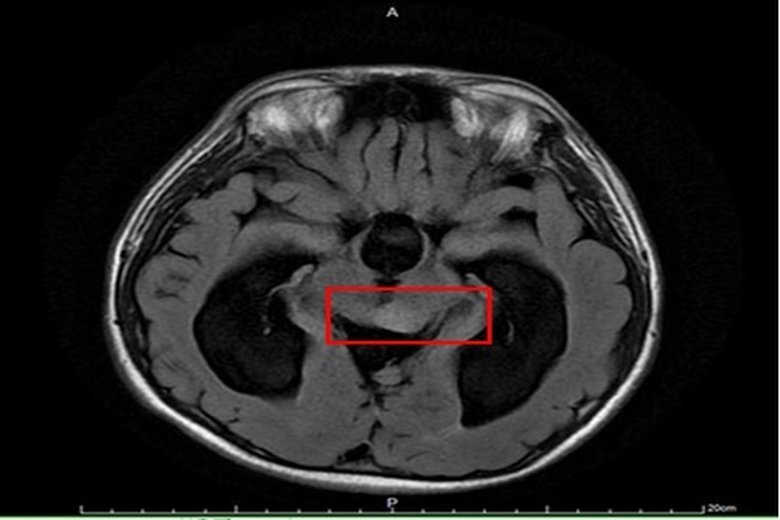

【新唐人亞太台 2020 年 09 月 23 日訊】15歲男孩因頭痛不適昏倒,被家人緊急送醫,經急診診斷疑為水腦合併癲癇,施以抗癲癇藥物治療。但男孩父母對癲癇病情仍有疑慮,故帶至臺大醫院新竹分院小兒神經科門診就醫。透過檢查,發現男孩眼動受限,眼睛無法往上看及往外側注視,醫師問診發現,他自小學四年級就開始頭痛,且因眼動受限而時常跌倒。經腦部核磁共振檢查確診為水腦併中腦腫瘤,立即安排手術治療。